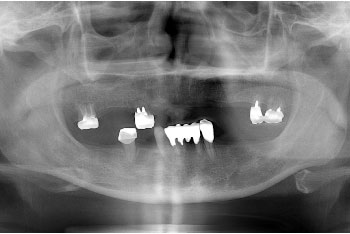

義歯が苦手ということで来院された患者様で、少しずつインプラントを増やし、最終的には悪いところを全てインプラントで補ったケースです。

最初は費用のこともあり、全ての欠損箇所をインプラントにすることは難しかったのですが、年毎に計画を立て、少しずつインプラント治療を進めていきました。

最終的には失われた部分は全てインプラントが入り、咬み合わせの改善も図ることが出来ました。今後は、ここまで治療していただけましたので、引き続きメインテナンスを通して今回の治療箇所及びその周りの歯の健康のお手伝いをしていきます。

治療の内容 インプラント治療11本、セラミック補綴5本を数年に分けて治療。

期間・回数 5年2ヶ月・31回(カウンセリング・検査を含む)

費用 自由診療:スタンダードインプラント✕11歯+セラミック補綴✕5歯 合計 4,410,000円(税込4,851,000円)